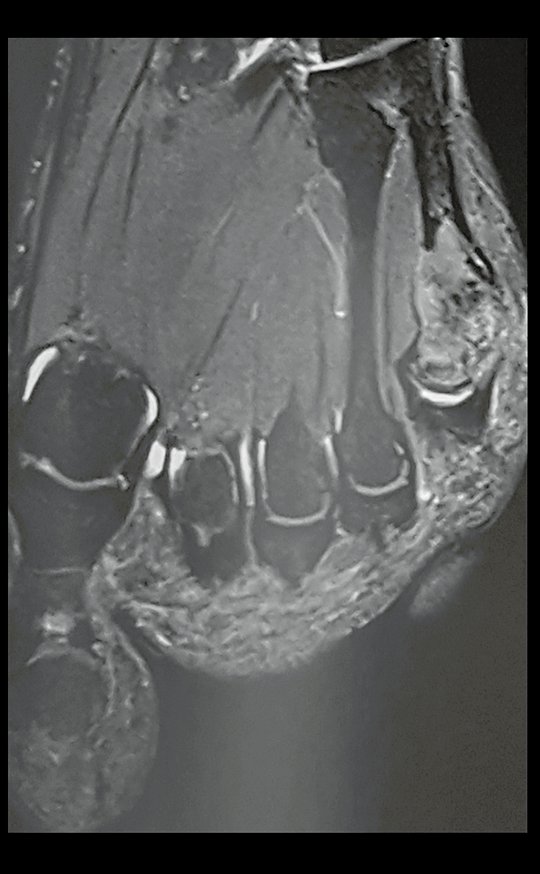

Fibroma desmoide del pie. Paciente de 43 años con “callo” en el quinto metatarsiano del pie izquierdo desde hace veinte años, que desarrolló deformidad, aumento de volumen y dolor en el último año.